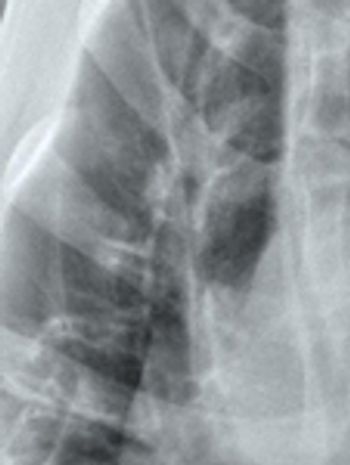

A bronchial pattern on radiographs indicates pathology involving the airways. It can be a subtle pattern to recognize, so let's look at some of the features.